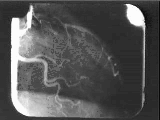

Heart X-ray Image Enhancement

Top: two corresponding angiographic images determined from period trace. Bottom: composite of 5 such corresponding images. Note additional structure visible in composite but not apparent in single raw images.